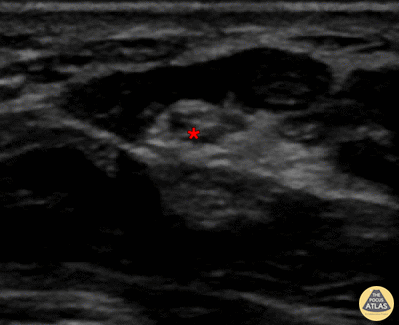

Out-of-plane median nerve block, with needle seen entering directly above median nerve, with anesthetic deposited superficial to median nerve (*). Denver Health Ultrasound Fellowship Archive